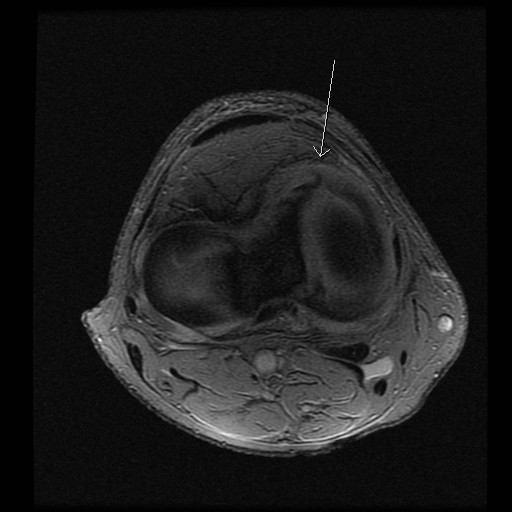

Mann i 30 årene. Vridningstraume 4 måneder siden; “ikke blitt bra ennå”, ønsket MR kne.

Diagnose: Bøttehank ruptur av fremre del av mediale menisk, såklat “double ACL sign”.

Sees også tydelig på coronale og axiale bilder (bilde 2 og 3):